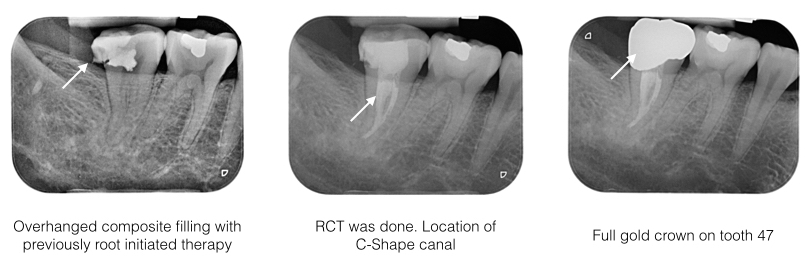

History : Mr MW is a 30 year old gentleman came with severe pain on the lower right molar. He claimed that a root canal was done recently on the offending molar tooth.

Examination : Tooth 47 has a large overhanged composite restoration, and slight swelling on gum. The tooth was very tender to percussion. Cold test and pulp test were negative. Radigraph showed tooth 47 has overhanged and leaking filling. Someform of root theraphy was initiated but the root canals have not been shaped, cleaned and filled.

Diagnosis : Acute apical periodontitis 47 with previously attempted root therapy.

Treatment : Old composite filling was replaced to to prevent any further ingression of microorganism into the root canal system. RCT was initiated under rubber dam isolation. Under microscope, there was one mesio lingual canal and a C-shape canal extending from mesiobuccal to distal. All canals were shaped with rotary nickel-titanium files and cleaned with ultrasonic irrigation. Canals were dressed with calcium hydroxide. The tooth was asymptomatic after 3 weeks review and was subsequently obturated to full working length. A full gold crown restoration was placed to prevent any coronal leakage.

RCT Case 3